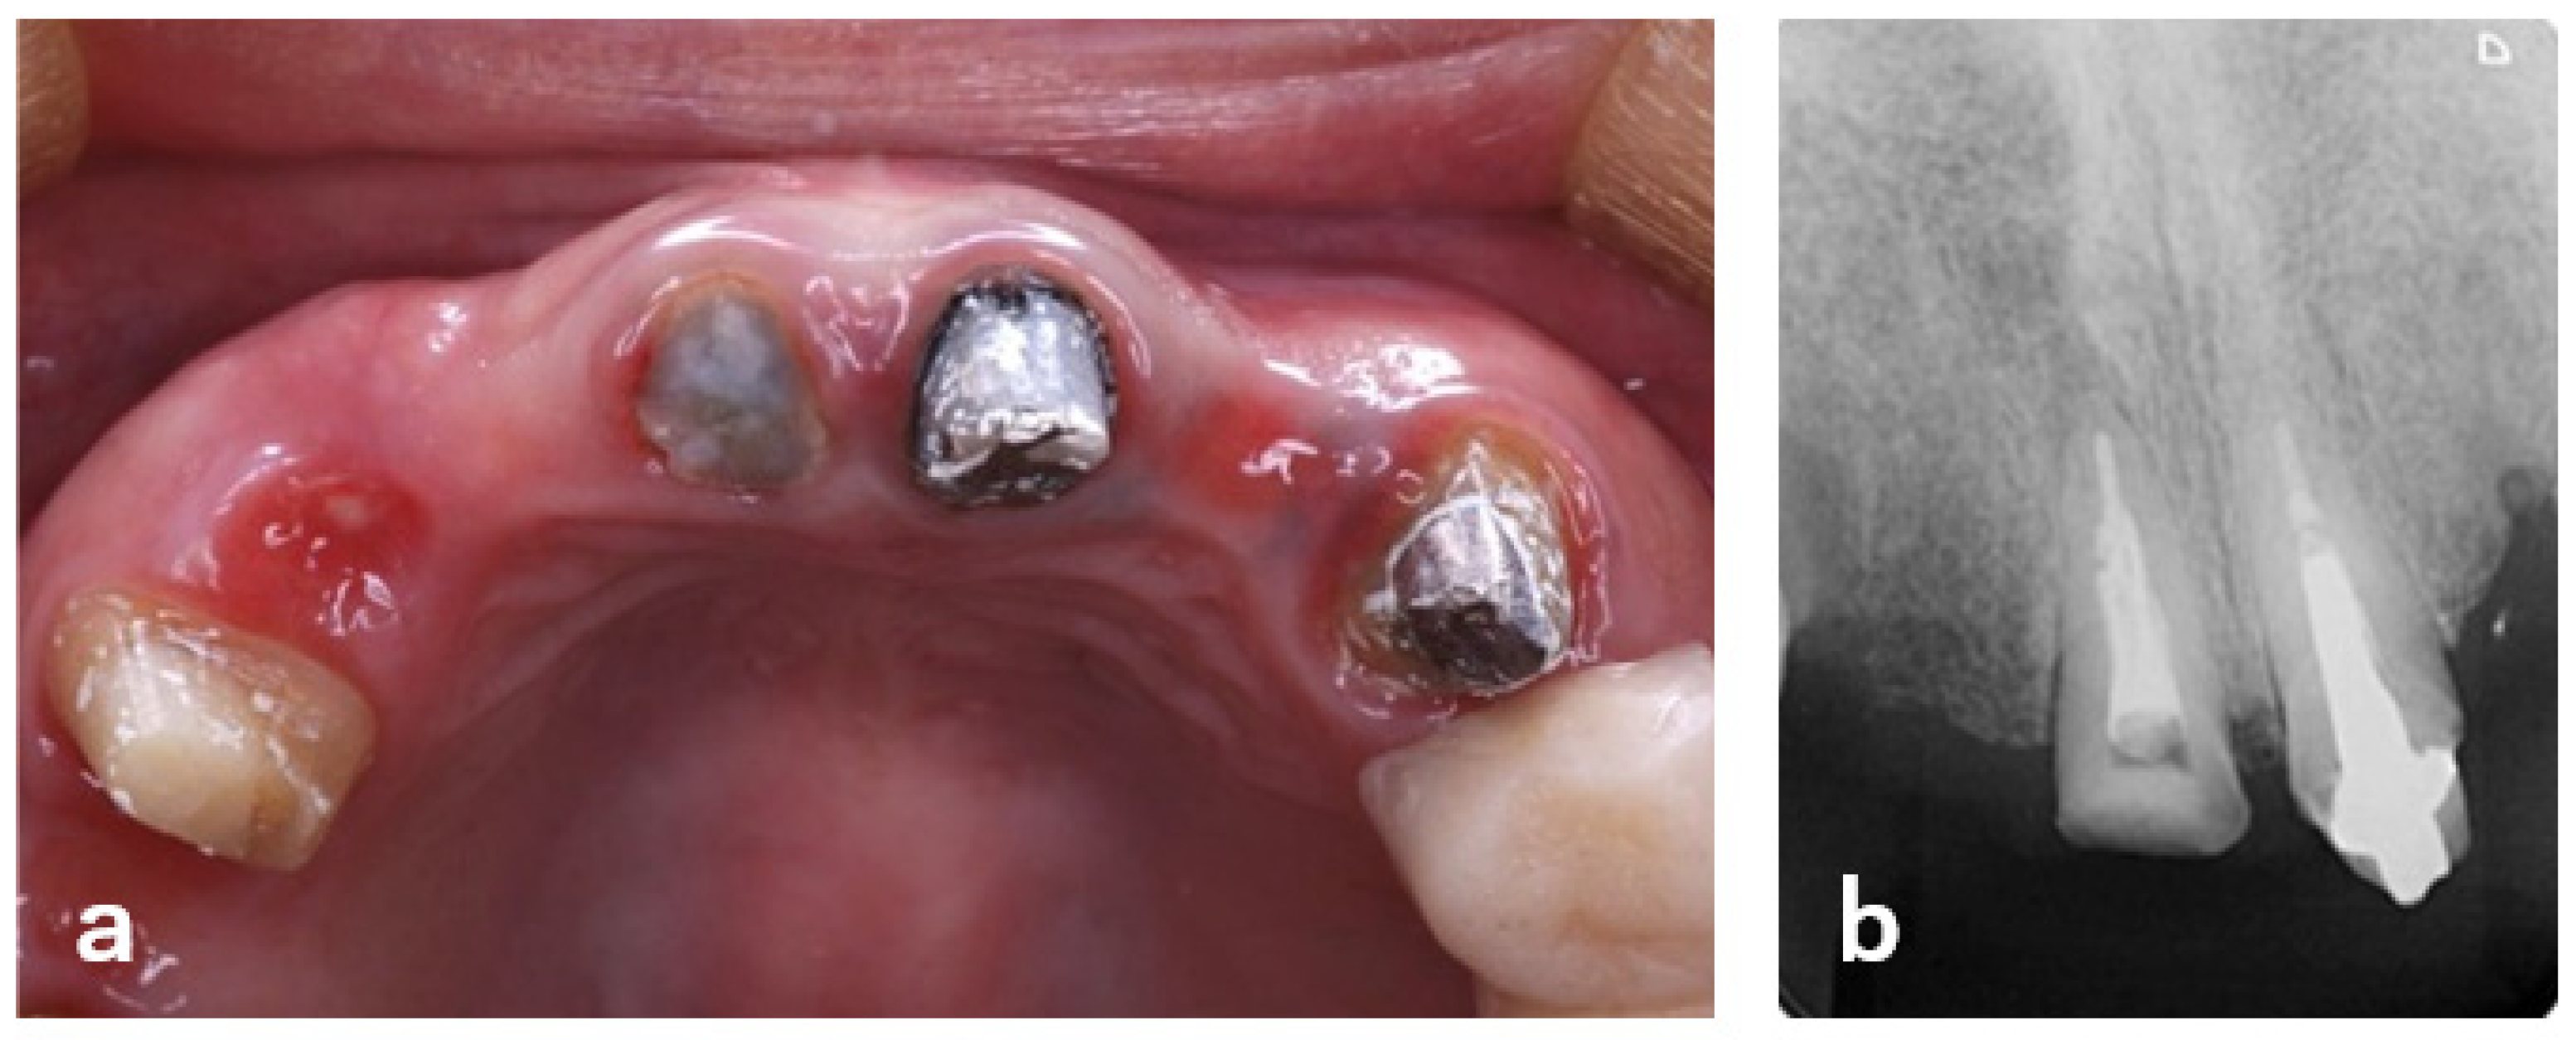

| 1 | Initial visit (August 2015) | Initial assessment & provisionalization | Assessment after traumatic event; long-span provisional restoration to re-establish posterior support and stabilize occlusion (Figure 1 and Figure 2) |

| 2 | Shortly after initial visit | Extraction of #13 | Vertical root fracture confirmed; extraction indicated (Figure 3) |